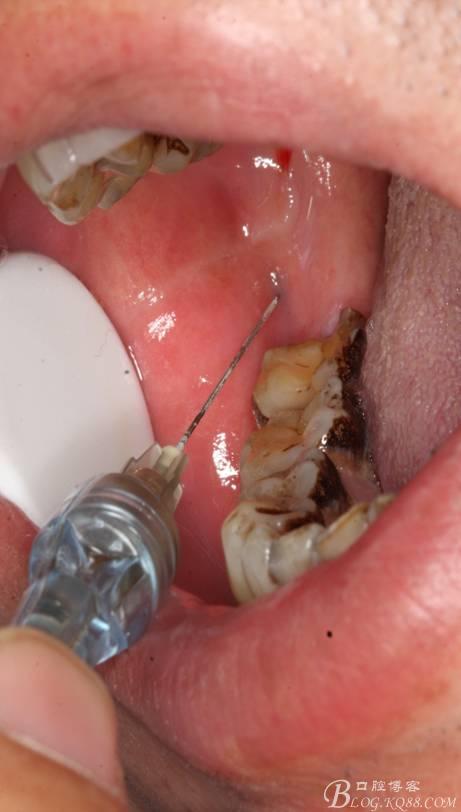

48未萌出,47遠(yuǎn)中可探及深約7mm的牙周袋。頰側(cè)47、48之間牙齦紅腫,有少量血性滲出。X線根尖片顯示:48牙冠反轉(zhuǎn)倒置,47遠(yuǎn)中牙槽骨吸收明顯。CBCT顯示:48牙冠近中面位于下頜管內(nèi)。

三、手術(shù)過(guò)程

1.麻醉